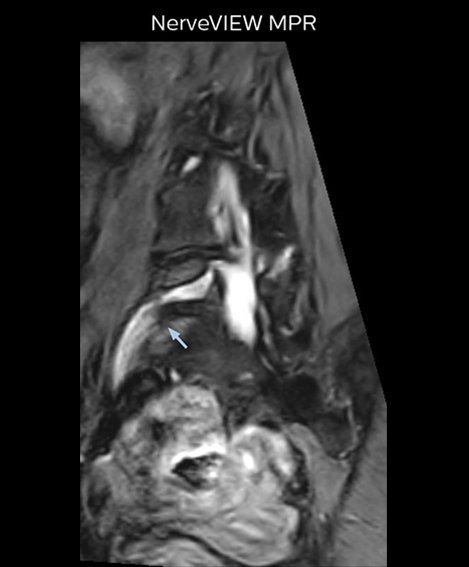

Distinguishing typical from atypical herniation informs the surgeon

“NerveVIEW is really useful for those cases where a nerve disorder is strongly suspected based on the clinical examination but our regular MRI images do not show any findings. These atypical herniations and spinal canal stenosis, occurring in 5% to 15% of the total lumbar herniation/stenosis cases are our main target when using NerveVIEW,” says Dr. Yabuki.

“Although symptoms of typical disc herniation and atypical hernia are very similar, the actual site of herniation is different. It is therefore important to characterize the nerve’s condition both inside and outside of the intervertebral foramina.

“Conversely, if we see no abnormality in NerveVIEW, we can assume at least that there is no severe condition that requires surgery. Like this, it can help us avoid unnecessary surgery. NerveVIEW can have a tremendous impact in this way.”

"Because NerveVIEW helps us identify the actual hernia site, it can inform selection of the surgical approach"

“Recently, the two surgical methods extreme and oblique lateral interbody fusion (XLIF and OLIF) have become mainstream for minimally invasive treatment of lumbar spinal canal stenosis and intervertebral foramen stenosis. With these surgical techniques, the spine is approached from the flank, and prior knowledge of the exact anatomy of the lumbosacral plexus would be extremely helpful. To that end, high slice resolution (less than 1 mm acquisition) that enables sharper sagittal MPR images will be needed.”

Because the obtained NerveVIEW images often exhibit a high signal in the intervertebral discs, we use partial MIP images to eliminate such intervertebral disc high signals. MIP image generation is based on the  center of the coronal stack, and RAO (right anterior oblique) and LAO (left anterior oblique) images rotated in the range of 45 degrees are used for diagnosis.